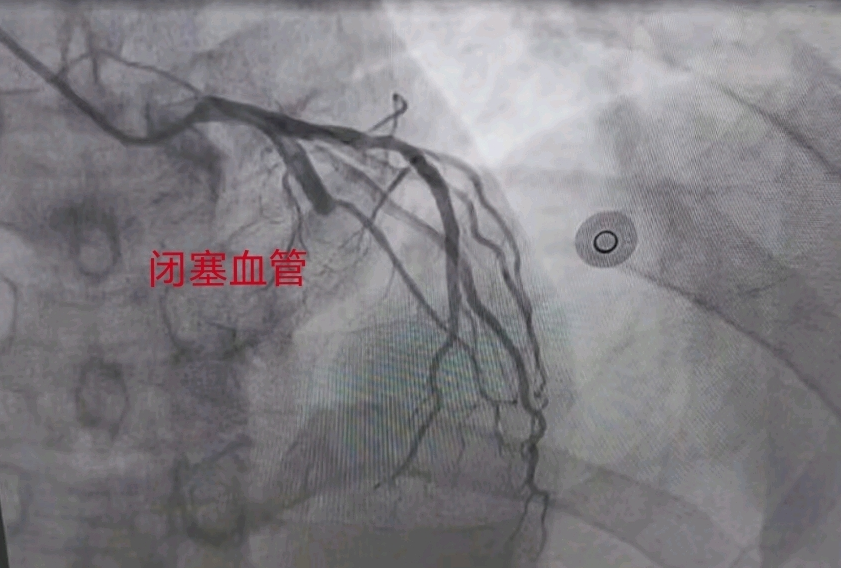

张副院长看过病人后分析患者中老年男性,既往有高血压危险因素, 此次急性发病,发病时间120分钟,心电图提示急性广泛前壁心肌梗死,根据最新《急性ST段抬高心肌梗死诊断与治疗指南》,需尽早开通梗死相关血管,恢复心肌再灌注,征得家属同意签字后,13时30分在心导管室行冠脉造影术显示前降支近段完全闭塞,结合患者病史及心电图变化,急诊予以开通前降支并植入支架1枚,手术用时33分钟,术后患者症状缓解,生命体征平稳,安全返回心内科重症监护室。